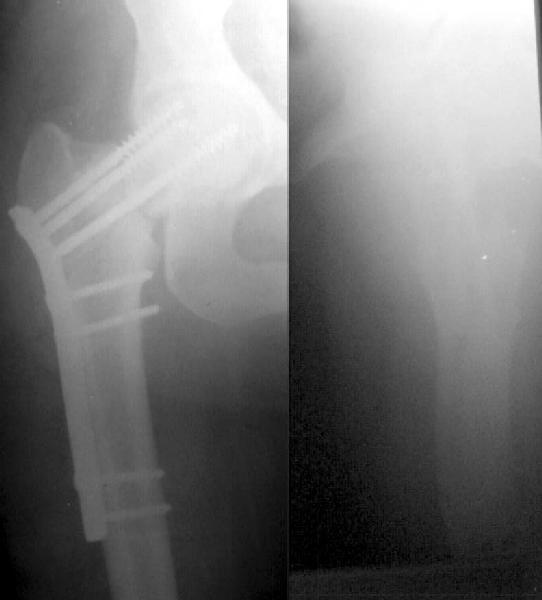

Alexander Chelnokov 07 Декабрь 2002, 17:54

Оперировали в четверг. Намаялись по полной программе. Репозиция закрыто не удавалась из-за рубцов. Когда обнажили область перелома, стало видно, что кость сильно склерозирована, почти не кровоточит (Педжета не Педжета, но что-то родственное - что?).

Сопоставили отломки, ввели спицы и спонгиозный винт в верхний полюс. При введении посадочного долота для клинковой пластинки (после предварительного сверления) бедро все равно раскололось на уровне клинка. Фиксатора, подходящего для этой ситуации, у нас не оказалось, поэтому взяли диафизарную компрессирующую пластину, смоделировали ее, рассверлили верхние отверстия и ввели еще два спонгиозных винта 6,5 ммм в шейку сквозь нее. Скомпрессировалось хорошо, головка тоже очень плотная. Понятно, особого удовлетворения сделанным нет.

Был бы признателен за комментарии. Все-таки, что за состояние у пациентки? Какая дополнительная информация помогла бы разобраться?

Если выявится несостоятельность фиксации до сращения шейки (что интуитивно кажется очень вероятным), что делать дальше?